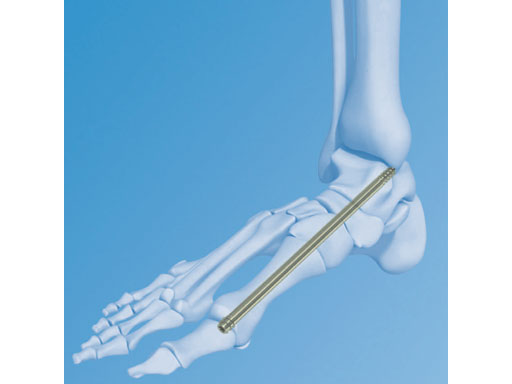

6.5 mm Midfoot Fusion Bolt

Per-Henrik Agren, Andrew Sands

The Midfoot Fusion Bolt (MFB) is a solid 6.5 mm intramedullary implant that can be used to stabilize and fuse the medial columnthe metatarsocuneiform, naviculocuneiform, and talonavicular joints. Alternative uses of the MFB may also be for fusing the lateral column, calcaneocuboid, and 4th metatarsocuboid joint. The MFB aims to achieve permanent fusion of these joints in patients suffering from gross instability such as Charcot neuroarthropathy with or without collapse of the midfoot. The midfoot fusion bolt is a headless solid bolt. It enhances stabilization and alignment, restraining shearing and bending forces better than older implants (I-bolt, 6.5 mm cancelleous screw, and 6.5 mm and 7.3 mm cannulated screws). The MFB is recommended for stabilization of the medial column or fixation of the lateral column. The bones and joints are aligned, measured and drilled with cannulated instruments. The guide wire is removed. The bolt is inserted through the track created by the 5.0 mm drill. Controlled compression may be applied by the T-handle during insertion. After insertion, the bolt head is completely countersunk preventing soft tissue or joint irritation. A blunt tip prevents any damage to soft tissues if the MFB is overinserted.

The MFB is available in lengths of 50160 mm in titanium and stainless steel.